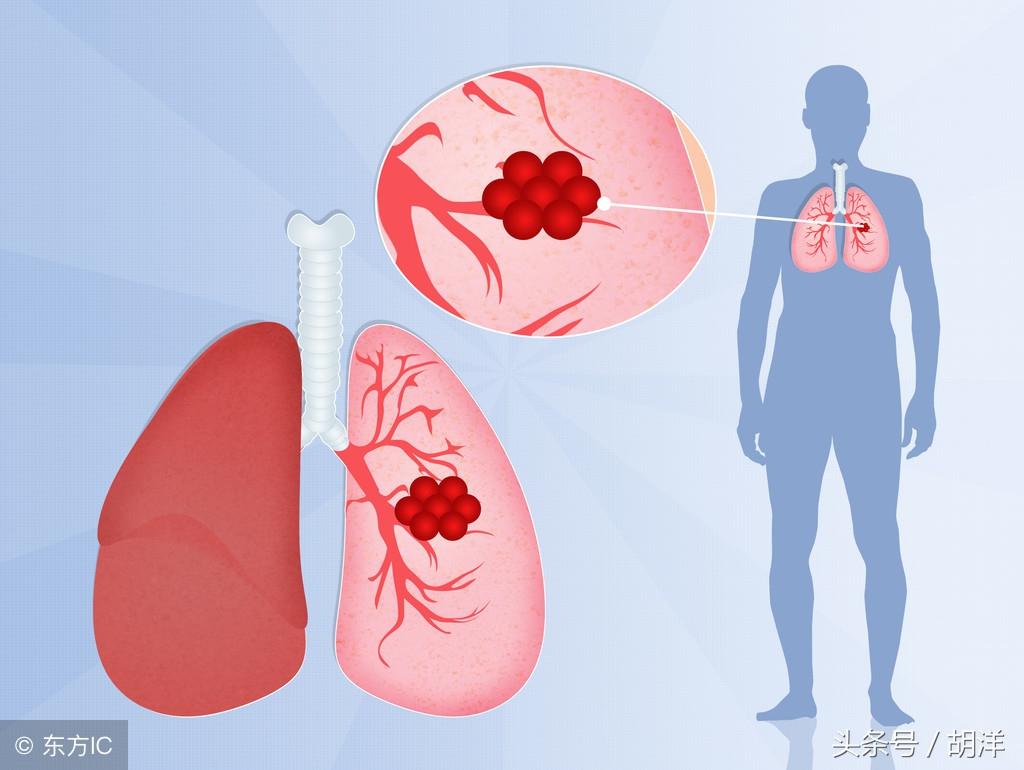

肺癌

肺癌也是较为常见的导致咯血的原因,恶性肿瘤细胞对于肺组织的侵蚀是其他疾病无法比拟的,几乎可以侵犯肺部正常组织中的所有结构,包括血管,另外,肺癌癌肿由于生长过快,其表面的细胞可能会因为得不到充足的血液供应而坏死,这样的坏死很容易产生渗血,是引起痰中带血的常见原因。

曲菌球

曲霉菌是一种常见的真菌,正常情况下,曲菌很少感染肺部结构正常,免疫力良好的人群,当肺部受到破坏,特别是形成较大空洞和支气管扩张时,曲霉菌可以趁机进入空洞扩张的支气管内与其中渗出的白细胞、纤维素等成分形成球状结构,成为曲菌球,曲菌球在空洞内能够自由的活动,对空洞壁有机械性的损伤,当损伤到管壁变异的血管瘤时,极有可能导致大出血。